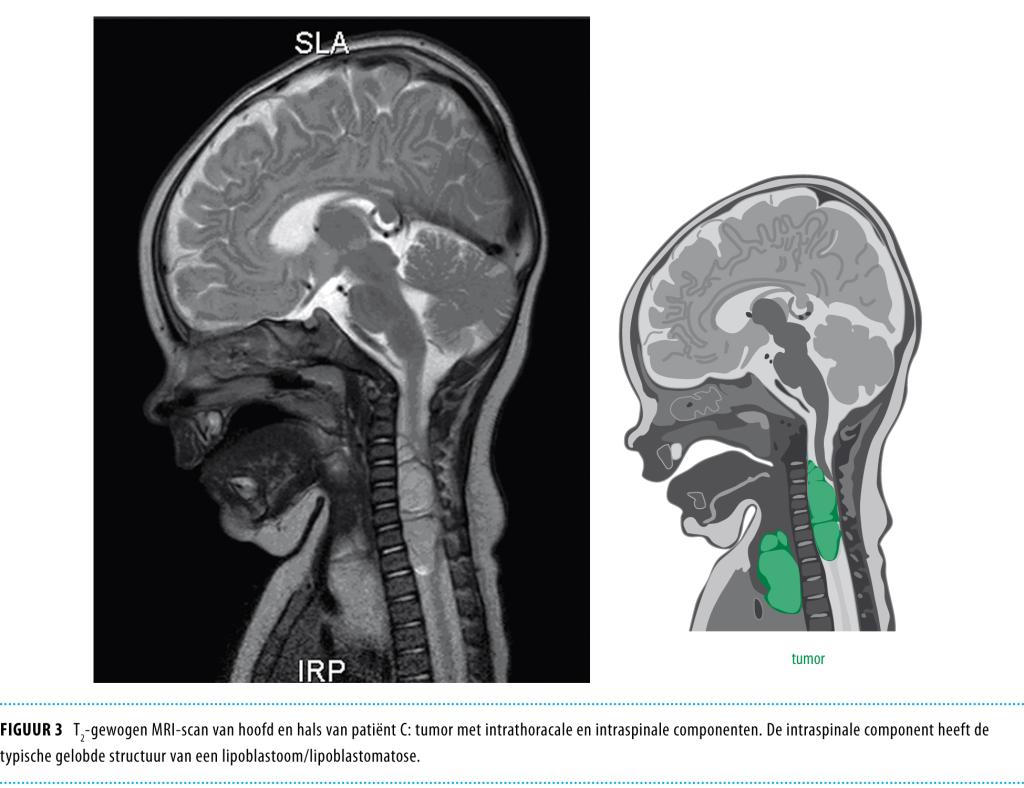

Patiënt C, een meisje van 5 maanden oud, werd gezien vanwege een torticollis naar links en pijn ter hoogte van de hals en de bovenrug. Een MRI-scan toonde een grote linkszijdige tumor met zowel een intrathoracale als een intraspinale component (figuur 3), meest waarschijnlijk lipoblastomatose of een hibernoom. De 2 componenten waren met elkaar verbonden ter hoogte van de rechter foramina intervertebralia van Cii tot en met Ti. Het intrathoracale gedeelte leidde tot een deviatie van de trachea en het bovenste mediastinum naar rechts. Het intraspinale gedeelte zorgde voor een massa-effect op het ruggenmerg, met als gevolg krachtsverminderdering ter hoogte van de bovenste ledematen, scheefstand van de nek en pijnklachten.

Figuur 3

Patiënte werd de volgende dag geopereerd, waarbij de intrathoracale component van het gezwel gedeeltelijk kon worden verwijderd. 3 dagen later volgde een ingreep om de intraspinale component te verwijderen; ook deze kon slechts gedeeltelijk worden verwijderd. Pathologisch onderzoek toonde een lobulair vetgezwel met variatie qua diameter van de vetcellen en de aanwezigheid van meerdere lipoblasten met ‘uitgeponste’ kernen. Tevens was focaal een myxoïde zone aanwezig. De diagnose ‘lipoblastomatose’ werd gesteld. Cytogenetisch onderzoek toonde een translocatie tussen chromosoom 8 and 9: 46,XX,T(8;9)(q13;p24), wat de diagnose ‘lipoblastomatose’ bevestigde. Postoperatief bleek de patiënte een rechtszijdig syndroom van Horner te hebben, dat na 3 jaar follow-up nog steeds aanwezig was.